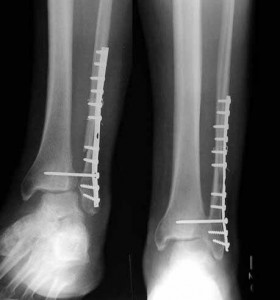

• The high ankle or syndesmosis sprain is an injury to the ligaments that bind the two bones of the lower leg – the tibia and fibula – together at their lower end.  We see plenty of these in footballers as the result of a collision or tackle.

• A syndesmosis sprain occurs when a twisting force is applied to the outside of the leg whilst the foot is planted on the ground.  They are also seen when the foot is forcibly pushed upwards, literally forcing the bones apart – aside from the typical footy injuries, these are quite common in mountain bikers courtesy of poorly executed landings from jumps.

• In severe cases, where the ankle has become grossly unstable, a surgical repair is undertaken to screw the tibia and fibula back together.  The screw is usually removed 12 or so months after the initial operation, by which stage there should be sufficient healing to safely stabilise the joint.